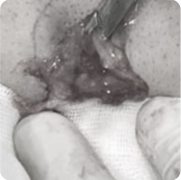

초반에는 간단한 절제로 수술이 가능하지만 방치하면 만성 염증 조직으로 인해

절제 범위가 커지고 흉터도 크게 남게 됩니다.